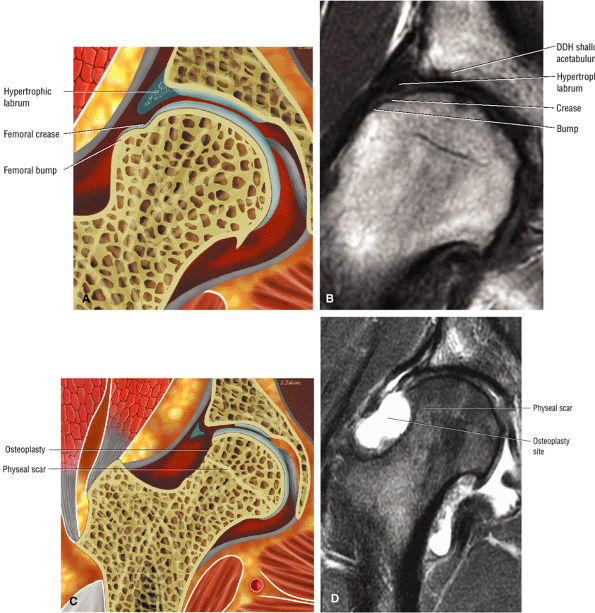

In DDH the labrum may be hypertrophic and associated with a femoral head chondral crease.

An anterosuperior cleft (Fig. 3.61) may be seen as a normal variant in the presence of a normal lateral acetabular labrum. On anterior coronal or sagittal images, this cleft is seen as a partial undercutting of the labrum on a single image. The extension of fluid into this cleft occurs from the femoral side. It may be more commonly seen in labral hypertrophy associated with mild developmental dysplasia of the hip (DDH).

An enlarged or hypertrophied labrum may occur in patients with mild DDH.17 We have observed a femoral head chondral crease (Fig. 3.66) in these patients, creating a demarcation trough medial to a femoral head bump immediately proximal to the physeal scar. Patients who demonstrate femoroacetabular impingement (or lateral acetabular rim syndrome in DDH) also have direct impingement between the lateral acetabular labrum and the femoral head.

patient. Unfortunately, the hypertrophic labrum is exposed to greater joint reaction forces and is at an increased risk for symptomatic tearing. The acetabular labrum may also become inverted, entrapped, and subsequently torn. Direct contact between the hypertrophied labrum and the femoral head chondral surface may produce a chondral crease demarcating a femoral head bump formed proximal to the physeal scar. This finding is associated with a lateral acetabular rim or the DDH equivalent of FAI. Anterior coronal MR images evaluated at the level of the anteriormost portion of the femoral head are sensitive to asymmetry in the slope of the acetabulum. The anterior acetabular roof should maintain a relatively horizontal slope and not open up or deviate from the horizontal plane.

FIGURE 3.101 ● (A) DDH associated with longitudinal tearing of a hypertrophied labrum. The shallow slope of the acetabulum is demonstrated. The transverse angle of the osseous acetabular rim affects the degree of lateral coverage and is increased in adult DDH. (B) The normal angle of 40° is shown in contrast to (A).